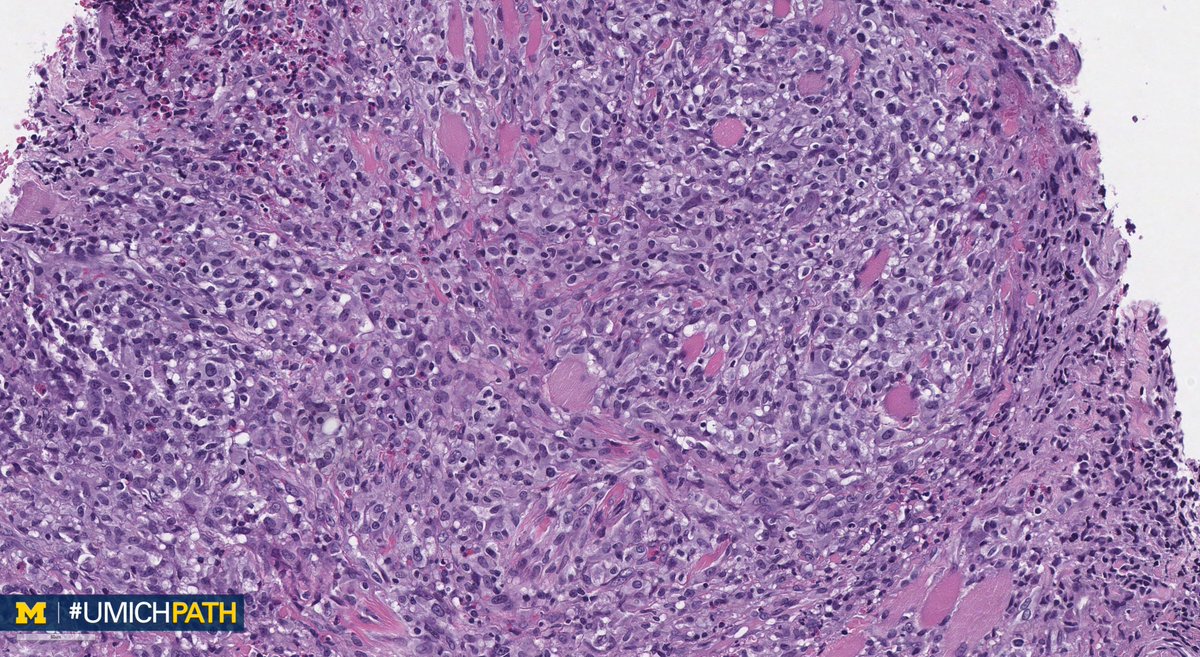

A: (Müllerian) adenosarcoma. Malignant stroma w/ associated benign epithelium (endometrioid or metaplastic); has “Phyllodes-like” architecture w/ stromal condensation. Can be low grade or have sarcomatous overgrowth (>25%) w/ high grade or heterologous sarcoma. #GYNPath #DailyDx